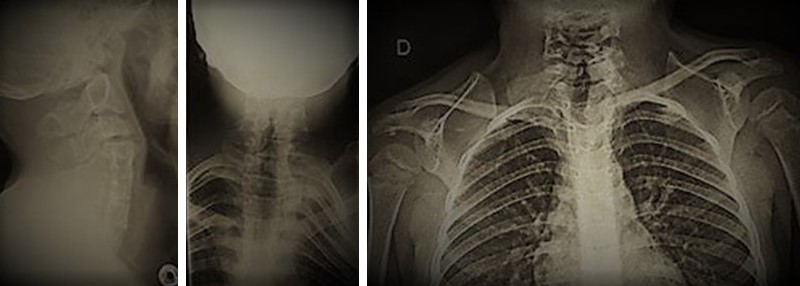

Diagnostic imaging examples of Klippel-Feil Syndrome and Sprengel Deformity, differing views.

Klippel-Feil Syndrome is a rare disorder that we learn about in many of our radiology classes. It is when two or more vertebrae in the neck are fused together from birth. People diagnosed with this syndrome may present with a short neck and limited movement, along with pain.

Sprengel deformity is commonly associated with Klippel-Feil Syndrome, and is a rare congenital disorder in which the scapula is too high on one side of the body. The main signs and symptoms of Sprengel deformity are limited or restricted movement of the arm and shoulder blade, as well as the cervical spine. Some individuals may present with neck deformities as well, ranging from torticollis to severe spine deformity. CT scans and MRI are commonly used to confirm a diagnosis of Sprengel deformity.